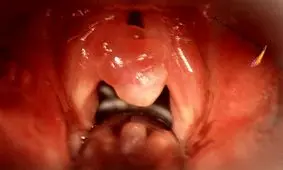

پولیپ یک توده کوچک از سلول هاست که داخل بدن رشد می کند. پولیپ دو نوع است یک دسته آویزان از ساقه هستند که پزشکان به آن ها پولیپ پایه دار یا pedunculated می گویند.